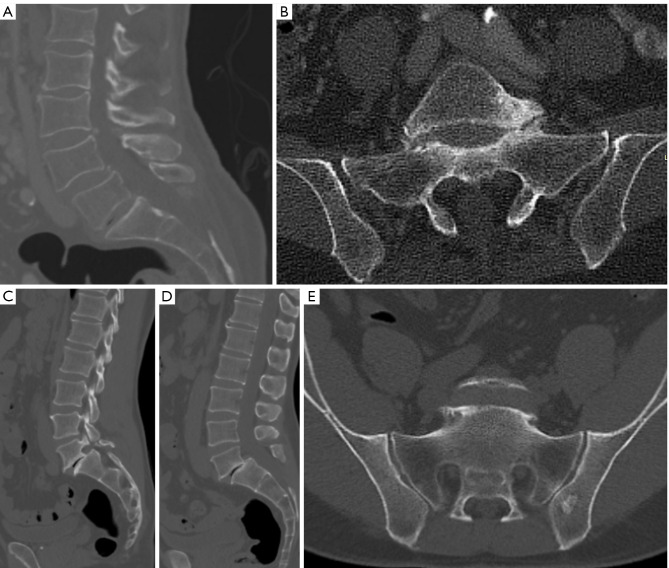

Background: Spondylolisthesis is defined as the anterior or posterior translation of one vertebral body over another. Spina bifida occulta (SBO) is a developmental anomaly characterized by the incomplete fusion of the laminae of one or more vertebral arches along the midline. Currently, there is no documented prevalence of SBO in patients with degenerative spondylolisthesis (DS) undergoing spinal surgery. This study aims to estimate the prevalence of SBO in patients with DS undergoing spine surgery and compare it with that in patients with isthmic spondylolisthesis (IS) undergoing surgery.

Methods: Our study is a cross-sectional retrospective review of consecutive patient records from two major tertiary hospitals in Sydney, Australia, covering the period from January 1st, 2015 to December 31st, 2023. Patients diagnosed with spondylolisthesis at spinal levels L4/L5 or L5/S1 were identified and screened for the presence of SBO.

Results: Among the patients who underwent spinal surgery, 23.4% were found to have spondylolisthesis due to either degenerative changes or isthmic pars defects at L4/L5 or L5/S1. Within the DS group, the prevalence of SBO was 11.9% (all at the S1 level), while 24.7% of the IS group exhibited SBO. The male-to-female ratio for patients with IS and SBO was 3.6:1, compared to 0.66:1 for those with DS and SBO.

Conclusions: SBO is a frequently overlooked anatomical variation in adult spine surgery, particularly in cases of degenerative and IS. With a prevalence of 11.9% in DS, it is crucial for spine surgeons to be vigilant, especially during open posterior lumbar spine fusion surgeries, to prevent unintended durotomy and neurological damage. Awareness of the absence of the S1 spinous process is essential for effective surgical planning, particularly when using navigated spinous process clamps for pedicle screw placement.